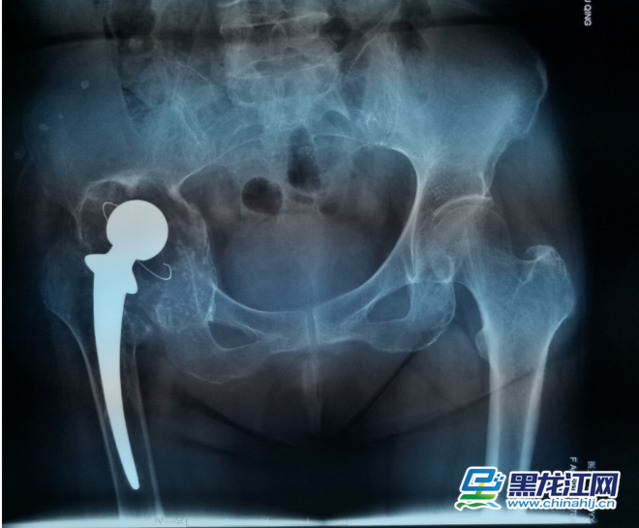

为了确保手术顺利,手术前,耿硕教授根据患者的影像数据,经过三维重建,真实复原了患者的右髋关节和盆骨模型。借助这一模型,耿硕教授可以全面精准地了解患者的关节结构,骨质情况等重要信息,为术前制订精确地手术方案提供了重要的依据。手术当日,耿硕教授手术团队按照术前模拟,顺利地将金属假体精准地安放在髋关节内。经过一周的康复,患者已顺利下地行走并康复出院。

据毕郑刚主任介绍,3D打印技术通过计算机与影像数据和材料技术的结合,可以制作出准确度惊人的器官模型和假体。用3D打印技术进行术前指导,可以让医生在手术前为风险较高的复杂手术制定手术方案,减少手术风险,提高手术的精确性。